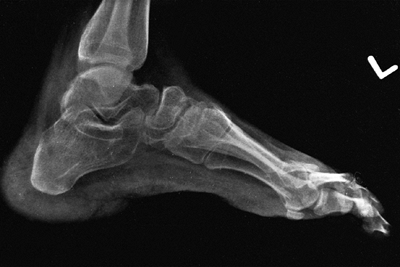

![]() |

Figure 16.7 This Charcot degeneration occurred in a 16-year-old, L-5 paraplegic girl who refused to wear her ankle-foot orthosis.

|

children with low lumbar levels of function. This deformity can limit